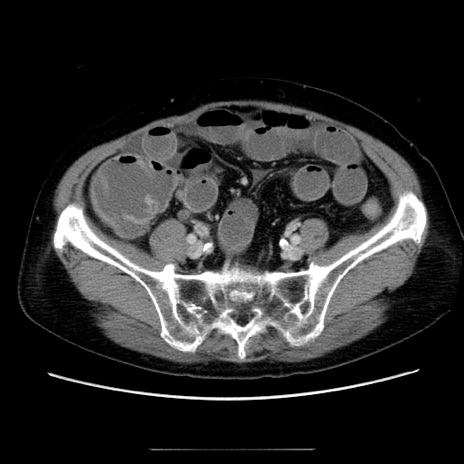

冠状断像

症例5(横断像)

【症例】70歳代女性

【主訴】お腹が張る

【現病歴】1週間くらい前から腹部膨満の自覚あり。昨日夜から増悪したため、本日救急外来受診。

【身体所見】意識清明、BT 36.5℃、BP 165/106mmHg、HR 80bpm、SpO2 98%、腹部:膨満、軟、自発痛・圧痛なし、触診にて不快感あり、腸蠕動音:減弱

【データ】WBC 12600、CRP 1.04